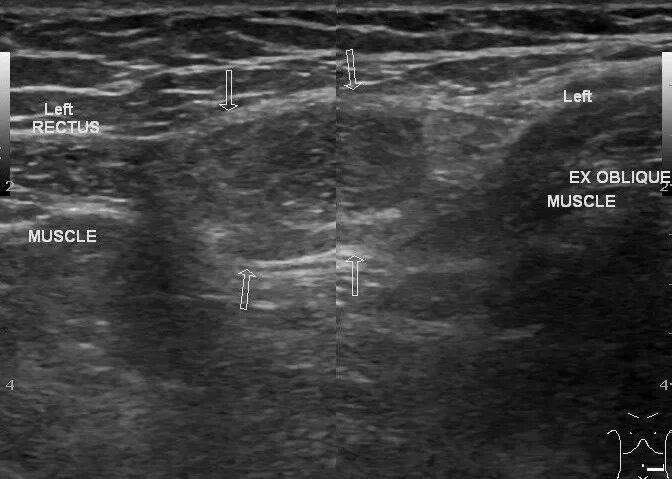

Грыжа спигелиевой линии